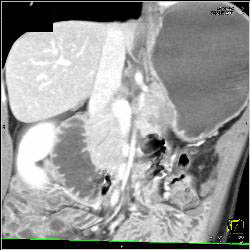

Infiltrative Carcinoma With Implants and Gastric Obstruction